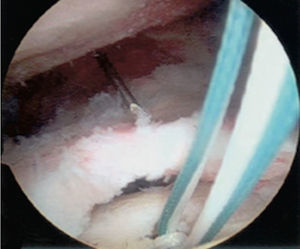

En la técnica de doble fila se colocan uno o dos anclajes mediales en el borde articular de la cabeza humeral, se pasan puntos sencillos a través del tendón y se anudan las dos suturas de cada anclaje con nudos deslizantes bloqueados. Los anclajes laterales se colocan en el borde lateral de la tuberosidad mayor y se anudan con las suturas mediales, ya sea con nudos deslizantes bloqueados o con los sistemas de no nudos existentes en el mercado. Una de las principales complicaciones en la reparación del manguito de los rotadores es la rerrotura, pero es muy importante tener en cuenta que en muchas ocasiones no existe una correlación directa entre una rerrotura, ya sea parcial o completa, con los resultados clínicos y funcionales44. Sin embargo, existe una relación directa entre la cicatrización y la fuerza postoperatoria (figs. 17–19).